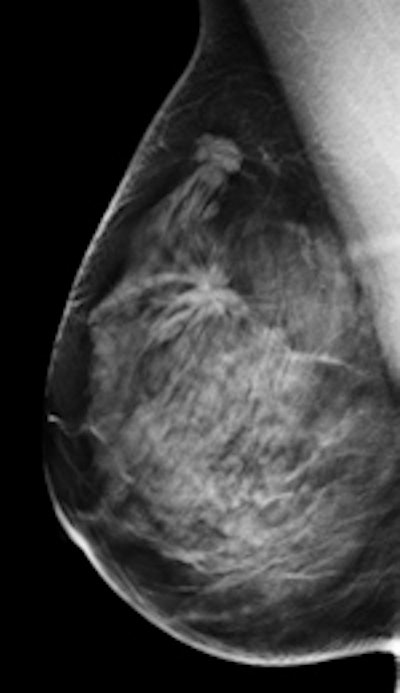

Left: Mediolateral oblique view of a patient with two malignant masses (invasive ductal carcinomas) using mammography. Center: Same patient viewed via craniocaudal mammography. Right: Same patient viewed on DBT. The spicules and tumor structures are better depicted by DBT. Copyright Dr. Gisella Gennaro.

Left: Mediolateral oblique view of a patient with two malignant masses (invasive ductal carcinomas) using mammography. Center: Same patient viewed via craniocaudal mammography. Right: Same patient viewed on DBT. The spicules and tumor structures are better depicted by DBT. Copyright Dr. Gisella Gennaro."Manufacturers are now progressively moving from prototype systems to clinical products, and exposure control is being optimized, allowing the acquisition of a DBT view at the same dose as a single mammography view," the authors noted. "This would permit use of a combined technique, like the one proposed in this work, at the same dose level as the reference standard (two-view digital mammography), with some benefits in terms of clinical performance, or, alternatively, use mediolateral oblique-view DBT alone at comparable performance to that of two-view mammography, but at half the breast dose."